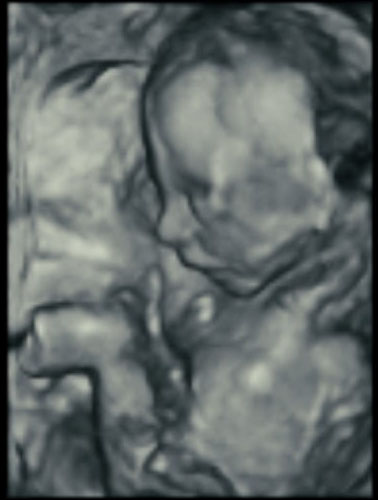

Here’s how ultrasound works in pregnancy: As early as 16 weeks, women can see a “fetal portrait” of their baby and determine its gender. Ultrasound technology has improved dramatically over the decades from flat, grainy black and white images to the current three-dimensional time experience.

Most hospitals offer some 3D scanning, but 3D ultrasound produces images that show the width, height and depth of a developing child. Rather than sending sound waves straight into the womb and recording when they bounce back as is common in 2D imaging, 3D ultrasound sends sound waves from different angles. A computer then renders a 3D image based on this data.

4D ultrasound adds movement as it occurs. The fourth dimension is time. You’re actually watching your baby live in 3D mode. How cool is that?